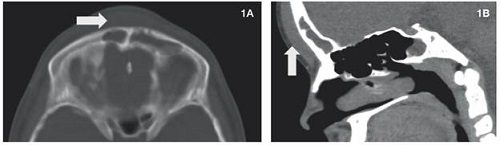

Caso 1

Paciente masculino de 12 años consultó por 8 días de cefalea, edema en región frontal, rinorrea purulenta y fiebre. Se realizó tomografia de cráneo simple que evidenció pansinusitis, con aumento de tejidos blandos en región frontal, sin evidencia de compromiso de la tabla ósea ni lesiones intracraneales. El paciente fue valorado por el servicio de otorrinolaringología (ORL), que realizó cirugía endoscópica transnasal y envió los cultivos respectivos. El resultado del cultivo fue Staphylococcus epidermidis y S. Aureus. Se inició antibioticoterapia y se continuó por cuatro semanas con mejoría del paciente, por lo cual se dio egreso con seguimiento por ORL (Figura 1).